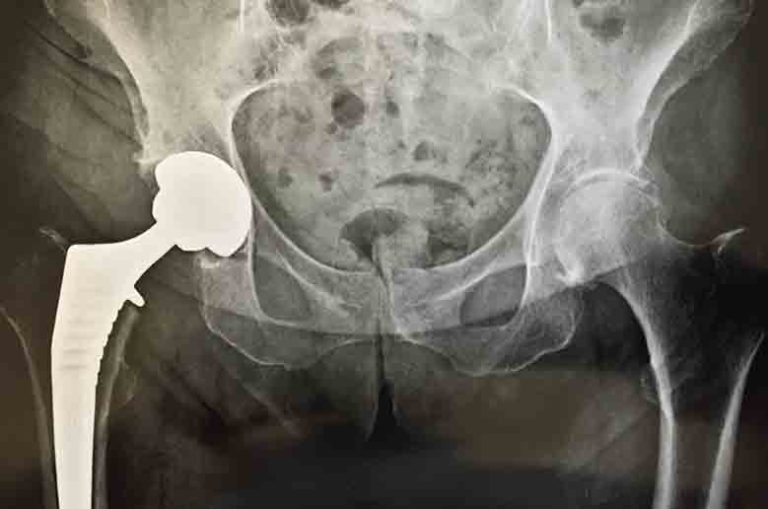

Chaque année, nous accueillons 10 millions de patients dans plus de 400 hôpitaux et centres de santé en Europe. La prothèse de hanche consiste à remplacer la tête du fémur et la cavité du bassin dans laquelle elle s’emboîte. L’intervention, qui dure de 1 à 3 heures, se déroule sous anesthésie générale ou locorégionale.. La luxation de la prothèse (déboîtement de la prothèse) Elle nécessite une remise en place de la prothèse sous anesthésie générale. Ce type de complication est devenue très rare (moins de 1% des cas), la prévention est réalisée par des recommandations faites par le kinésithérapeute lors du séjour à la polyclinique.

Surnommée l’« intervention reine de la chirurgie orthopédique », la prothèse de hanche est une opération très fréquente pour remplacer l’articulation de la hanche.. Vivre avec une prothèse totale de hanche. Les approches chirurgicales minimalement invasives pratiquées aux HUG respectent davantage les muscles de la hanche et permettent une récupération plus rapide. Les progrès de cette prise en charge portent également sur l’accompagnement lors du parcours de soins et sur la gestion de la douleur.